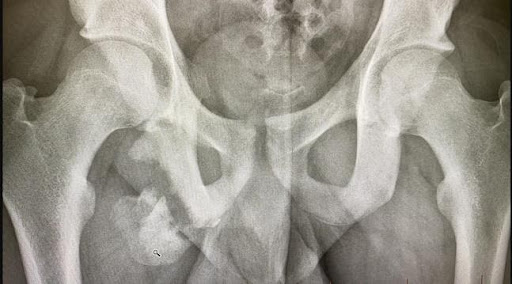

The mechanism of injury involved a sudden explosive sprint effort causing a massive avulsion of ischial tuberosity, including a part of the bony origin (see figures 12 and 13).

Figure 12

Figure 13 – MRI coronal right hip

This was treated as a hamstring tear for approximately a year. The young teenager subsequently developed disabling sitting pain interfering with studies as well as sciatic nerve irritation due to local compression. If this was identified early it could have been treated surgically.